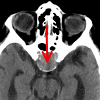

Определение хумекто-плечевого индекса. Метод оценки артериального кровотока с использованием ультразвукового сканера, с максимальной точностью определяющий уровень давления. При обследовании дается изображение степени сужения кровеносных сосудов. Он используется в диагностике артериального стеноза с целью выявления возможных причин стеноза, а также в послеоперационном периоде с целью контроля эффективности лечения. Техника неинвазивна, выполняется в амбулаторных условиях. Первичная подготовка для определения индекса голеностопного сустава не требуется, необходимо использовать специальное оборудование. С помощью манжеты для косвенного определения артериального давления точные данные записываются дуплексным сканером или доплеровским сканером.